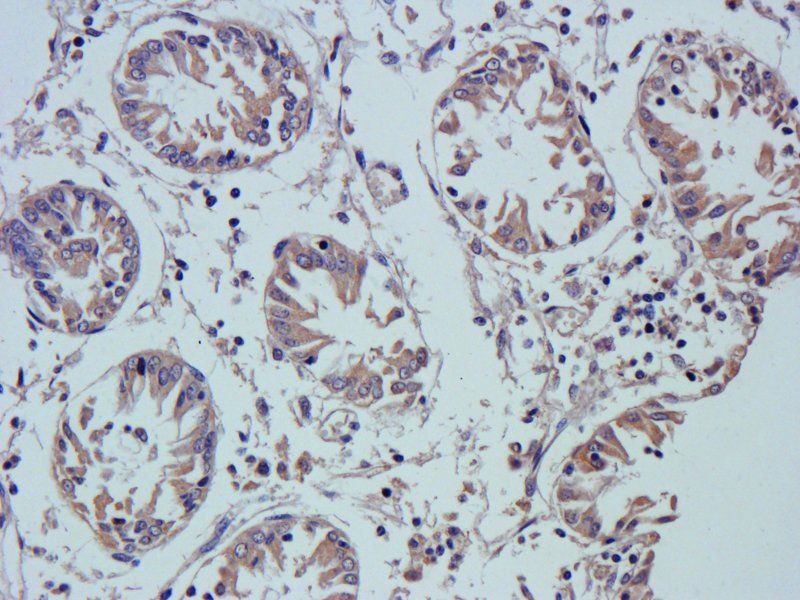

10 μg, 100 μg - Cubilin antibody [orb4997]Featured

ICC, IF, IHC-P, WB

Human, Mouse, Porcine, Rat

Rabbit

Polyclonal

Unconjugated

100 μg - PGP9.5 antibody [orb6713]Featured